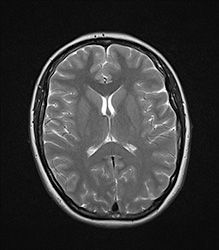

МРТ головного мозга

Головной мозг можно назвать непрерывно функционирующим компьютером, координирующим работу органов человека на протяжении всей его жизни. Стоит ли говорить о том, что любые нарушения в работе головного мозга чреваты серьезными проблемами со здоровьем. Вот почему качество метода исследования этого органа имеет особое значение. Одним из наиболее эффективных методов диагностики является магнитно-резонансная томография головного мозга МРТ

МРТ головного мозга — это абсолютно безболезненный неинвазивный (т.е. не требующий «проникающих» процедур) способ исследования целого ряда заболеваний нервной системы. В основе МРТ головы лежит свойство ядер атомов водорода возбуждаться под воздействием электромагнитных волн внутри напряженного магнитного поля. Полученные данные визуализируются с помощью современной компьютерной техники.

МРТ головного мозга ребенка в Москве, а также обследование взрослого человека, позволяет определить причину многих болезней – отклонения в развитии этого органа, разнообразные патологии и нарушения в его работе.

Магнитно-резонансная томография — это один из немногих методов исследования головы и головного мозга, который совмещает в себе два важнейших качества: безопасность, о которой мы уже упомянули выше, и эффективность. Получаемые по итогам МРТ головы снимки являются более четкими и детальными, что позволяет врачам получить полную информацию о состоянии здоровья пациента.